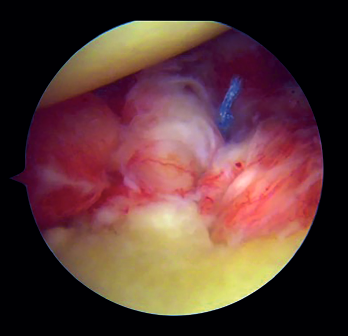

Introduction and fixation of the graft (Figure 4)

The cannula is removed from the anterior portal, from the posterior viewing portal, rotator interval is widened in order to facilitate introduction of the graft. Using both monofilaments, the graft traction threads are inserted from front to back. The graft is introduced into the joint, applying traction upon the threads from the posterior position. The graft is placed in line with the defect and within the capsulolabral structures. Once the graft is positioned in its final anterior position, the posterior buttons are placed by means of the traction threads and are fixed via a self-stabilizing running suture, tightening to 100 N with the help of a tensiometre, in sequence.

Figure 4. View from the posterior portal (left shoulder). Insertion of the graft by means of the traction threads and positioning in line with the bone defect.